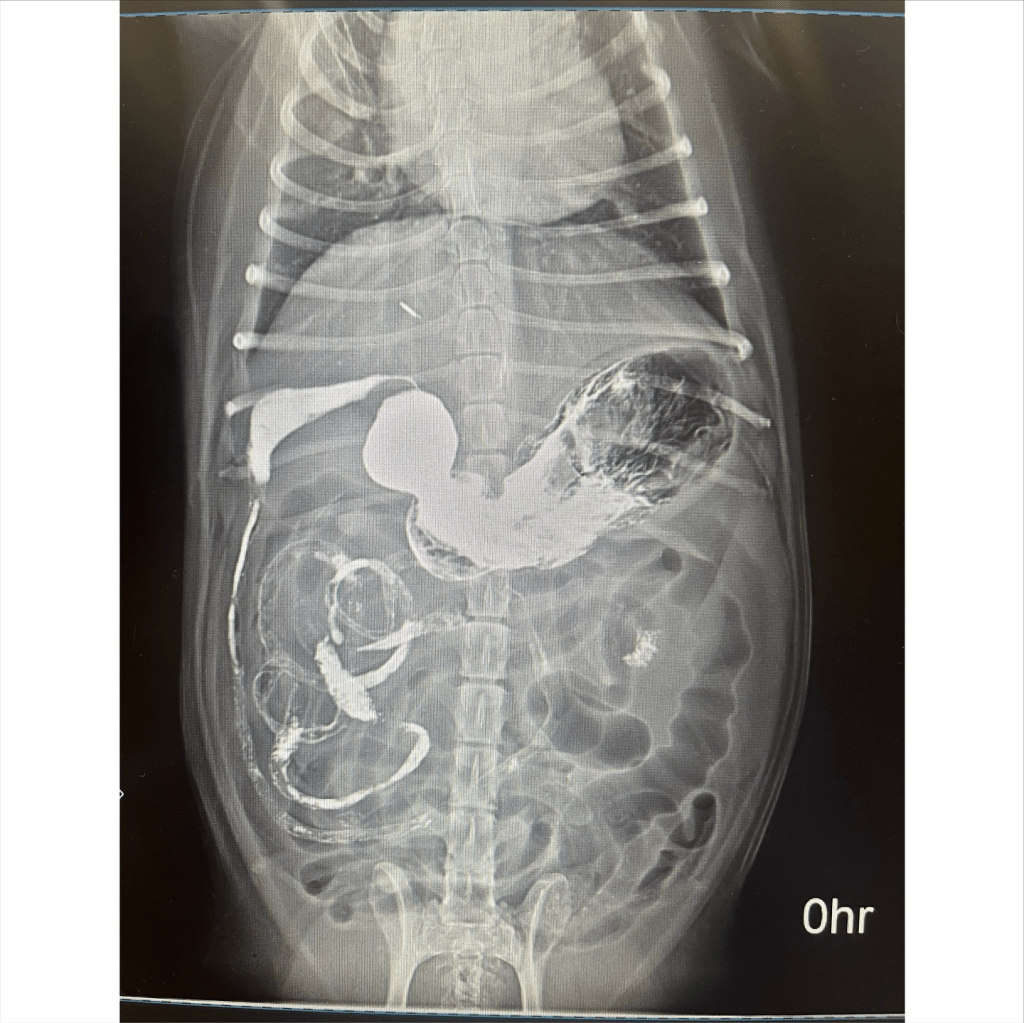

今天這位毛孩因為「吃了紙箱和眼鏡布」,造成腸胃不適,所幸透過內視鏡順利將異物夾出,避免了開刀的風險 ![]()

有些異物卡在胃腸道中,無法自然排出,必須靠內視鏡或手術處理!